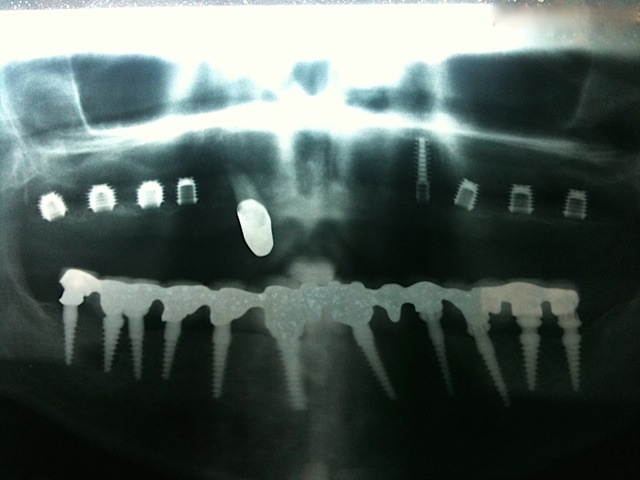

Komplett-Implantation: